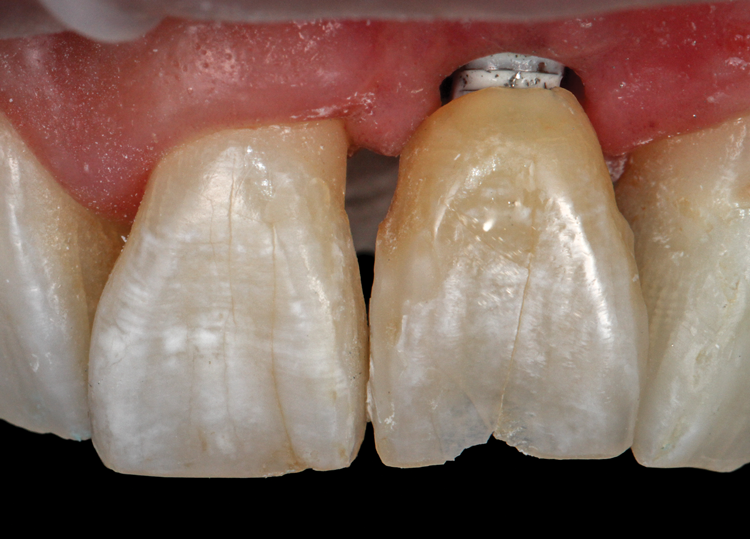

(45.) A patient presented for the replacement of the maxillary left central incisor with a bonded pontic made from the natural tooth, which was removed.

Figure 45